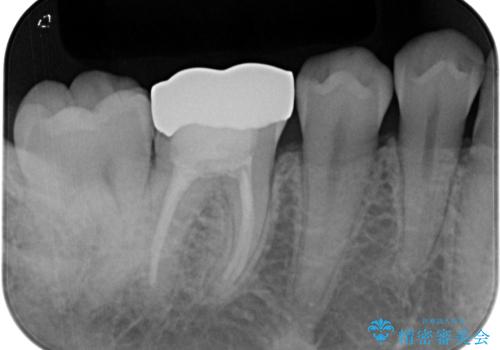

見た目、噛み合わせともに満足していただけました。

歯質と被せ物(クラウン)の境目も適合の良いものができました。